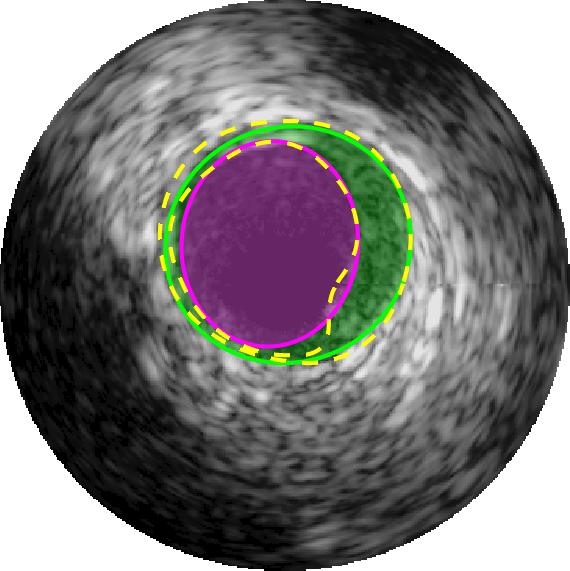

Qualitative evaluations are illustrated in Figure 4 and show the successful segmentation results of the proposed EREL selection strategy for 20 IVUS frames. The lumen areas are highlighted by the magenta colour while the media regions are green. Also, the manually annotated contours for both lumen and media are drawn as yellow dashed lines. As we can see, the chosen frames contain a variety of lumen and media morphologies.